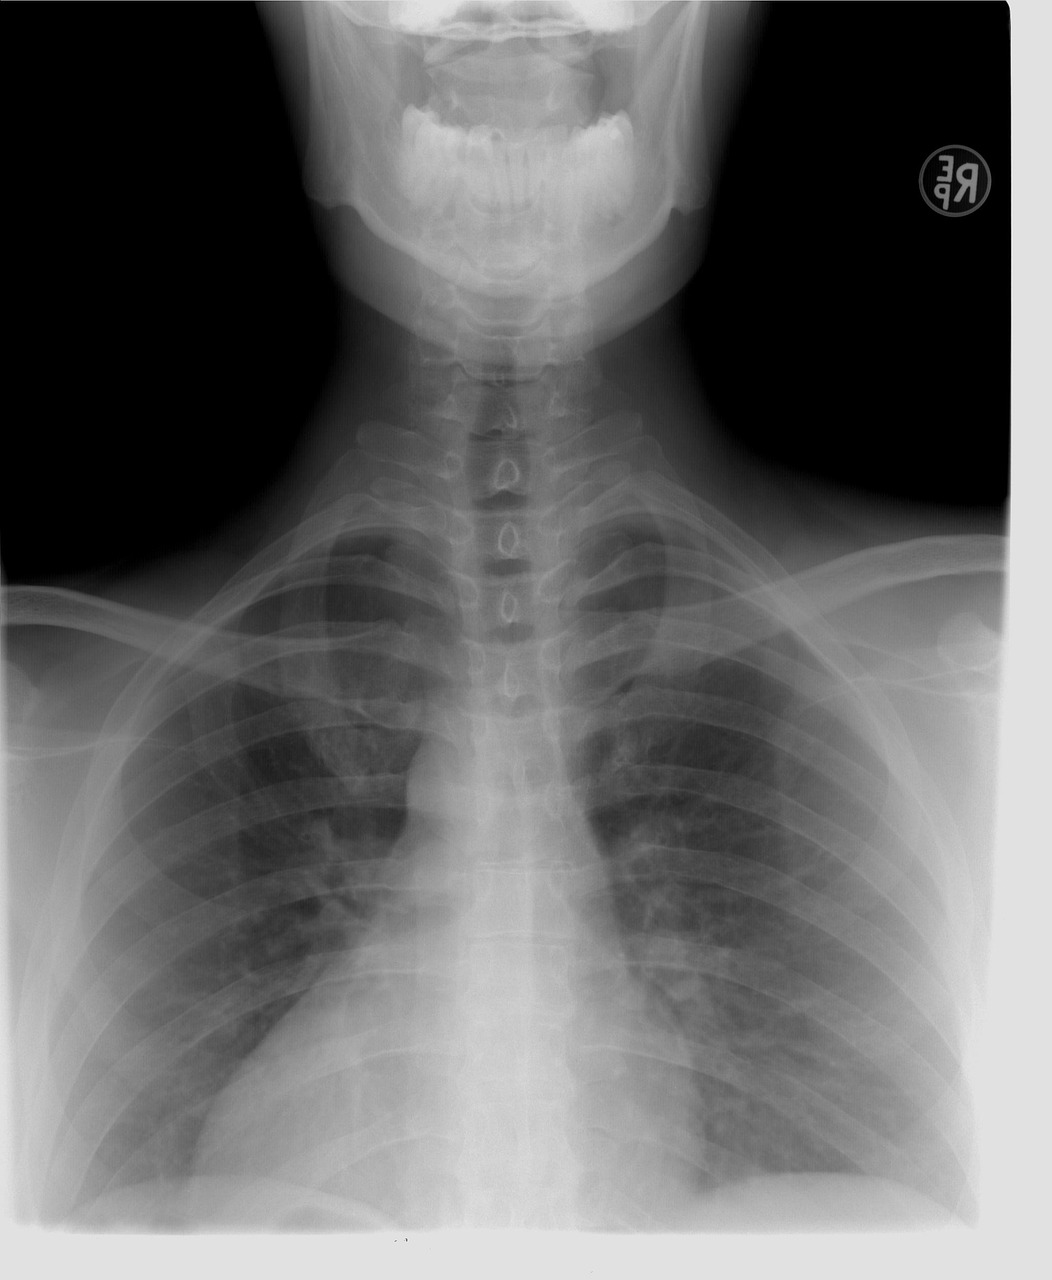

검사 방법 : 흉부 X-ray 촬영을 통해 폐에 결핵균 감염으로 인한 이상 소견이 있는지 확인합니다. 상의를 탈의하고 촬영하며, 임산부의 경우 반드시 사전에 의료진에게 알려야 합니다.

검사 목적 : 폐결핵은 호흡기를 통해 전파되는 전염병으로, 기침, 발열, 체중 감소 등의 증상을 유발합니다. 집단생활을 하거나 대중과 접촉이 많은 직업의 경우, 폐결핵 전파를 막기 위해 검사를 실시합니다.

흉부 X-ray 촬영 시 목걸이 등 금속 액세서리는 제거해야 합니다.

임산부이거나 임신 가능성이 있다면 반드시 의료진에게 알려야 합니다.